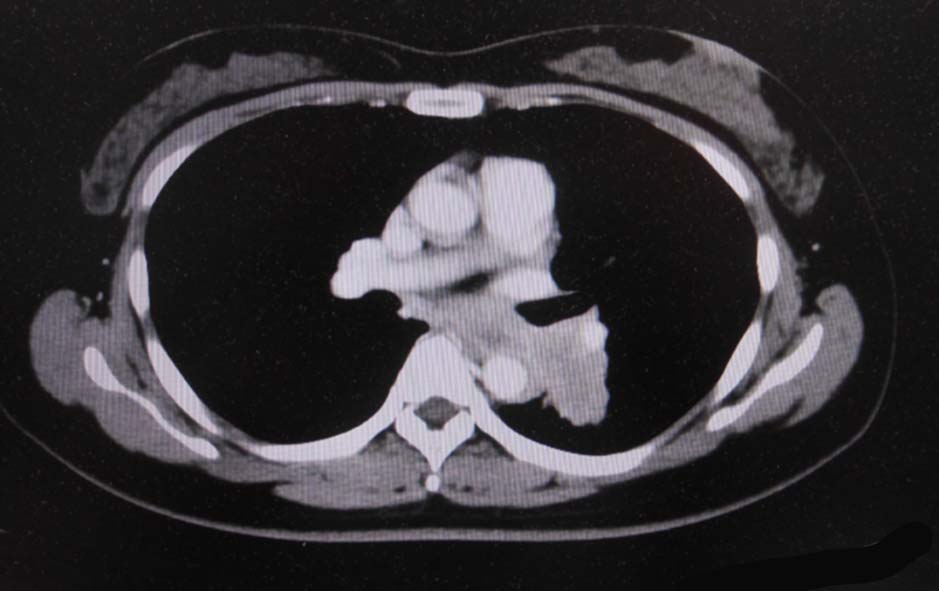

経過観察中に施行された胸部CTでは左肺癌が疑われた.精査加療目的に当院呼吸器内科を紹介受診.

CT画像:左肺から縦隔に及ぶ腫瘍(肺は単独病変. 肺内転移なし.),乳腺腫瘤,子宮腫瘤, 多発肝腫瘤あり.

CT画像および肺腫瘤生検組織